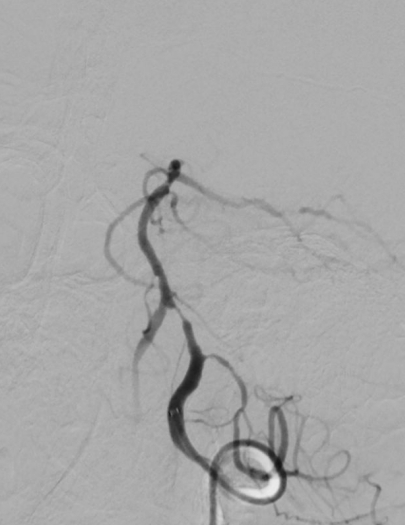

图片4.jpg

椎动脉狭窄                                                  椎动脉支架术后〔经桡动脉入路〕